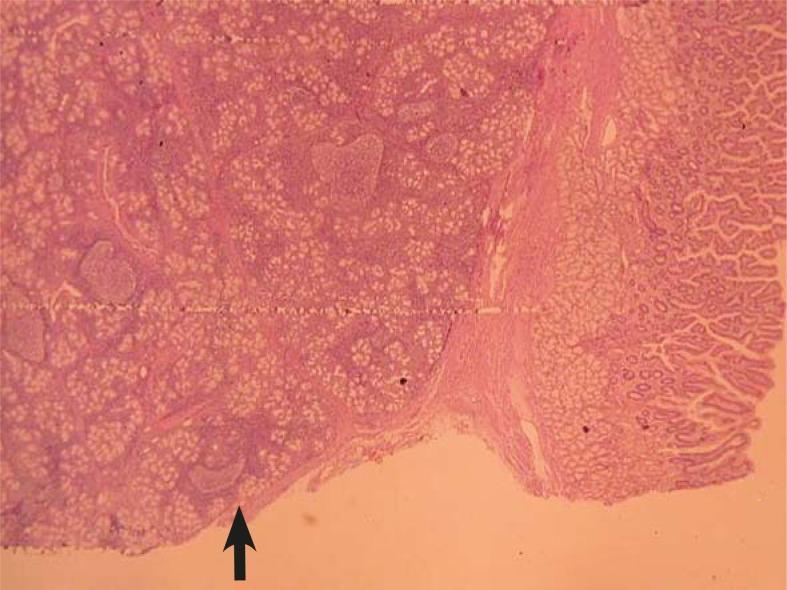

Brunner's gland adenoma (BGA) is a rare benign duodenal tumour proliferating from Brunner's glands. Here, we present a giant BGA leading to anaemia, with its clinical, endoscopic, radiological, surgical and pathological findings.

A 48-year-old Turkish man complained of a six months history of vague epigastric discomfort, loss of appetite and nausea after meals without vomiting. The physical examination had no unremarkable finding. Laboratory findings, including liver function tests, were within normal limits except a hypochromic, microcytic anaemia. The upper gastrointestinal endoscopic examination revealed a lobulated, red, polypoid tumour with a smooth surface covered with normal mucosa. The tumour was located on the anterior surface of duodenal bulb and had a wide base measuring 3.5 × 4 cm in size. Endoscopic ultrasonography revealed a submucosal polypoid mass located at the anterior surface of duodenal bulb. The endoscopic excision was tried but was not successful. The patient was operated and transduodenal polypectomy was done. The postoperative period was uneventful and the pathologic diagnosis was assessed as Brunner's gland adenoma. During the follow-up period, the endoscopic examination was normal at 12th month postoperatively.

BGA is a rare benign cause of anaemia that can be treated with excellent results.

布伦纳氏腺腺瘤(BGA)是一种罕见的良性十二指肠肿瘤,由布伦纳氏腺增生引起。本文报道了一例导致贫血的巨大 BGA,包括其临床表现、内镜、影像学、手术和病理特征。

一名 48 岁的土耳其男性,因上腹不适、食欲减退和餐后恶心(无呕吐)6 个月来就诊。体格检查无明显异常。实验室检查除小细胞低色素性贫血外,其余肝功能检查均正常。上消化道内镜检查发现十二指肠球部有一个分叶状、红色、息肉样肿瘤,表面光滑,覆盖正常黏膜。肿瘤位于十二指肠球部前壁,基底较宽,大小为 3.5×4cm。内镜超声检查显示十二指肠球部前壁黏膜下有一个息肉样肿块。尝试内镜切除,但未成功。患者接受了手术,行经十二指肠息肉切除术。术后恢复顺利,病理诊断为布伦纳氏腺腺瘤。术后 12 个月的内镜随访正常。

BGA 是一种罕见的良性贫血病因,治疗效果良好。